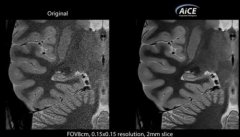

佳能医疗AI算法获FDA批准,将应用于公司的MR设备

MR 扫描也可以通过 AI 获取更清晰图像。 2020 年 3 月 18 号,美国佳能医疗宣布,其最新的人工智能Clear-IQ 引擎(AICE)已被 FDA 批准用于该公司的 Vantage Galan 3T 磁共振成像系统。 虽然,此前 AICE 已被...